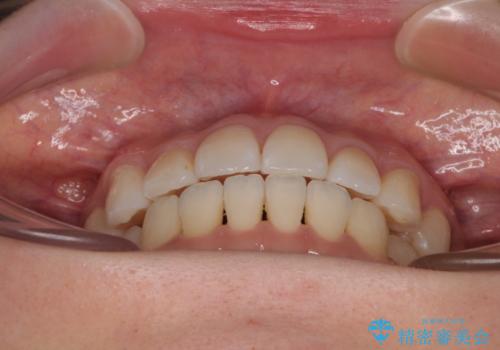

舌のトレーニングは不十分でしたが、1年半ほどで治療を終えることができました。

舌の突出癖が残っていると、容易に後戻りしてしまうため、トレーニングは継続するように指導しています。

- 前歯のデコボコと、上下前歯が接触せずに前に飛び出していることを気にして来院された患者様です。

舌の突出癖が強く、それが原因で上顎歯列全体が前方に突出し、上下前歯が接触できない状態となっていました。